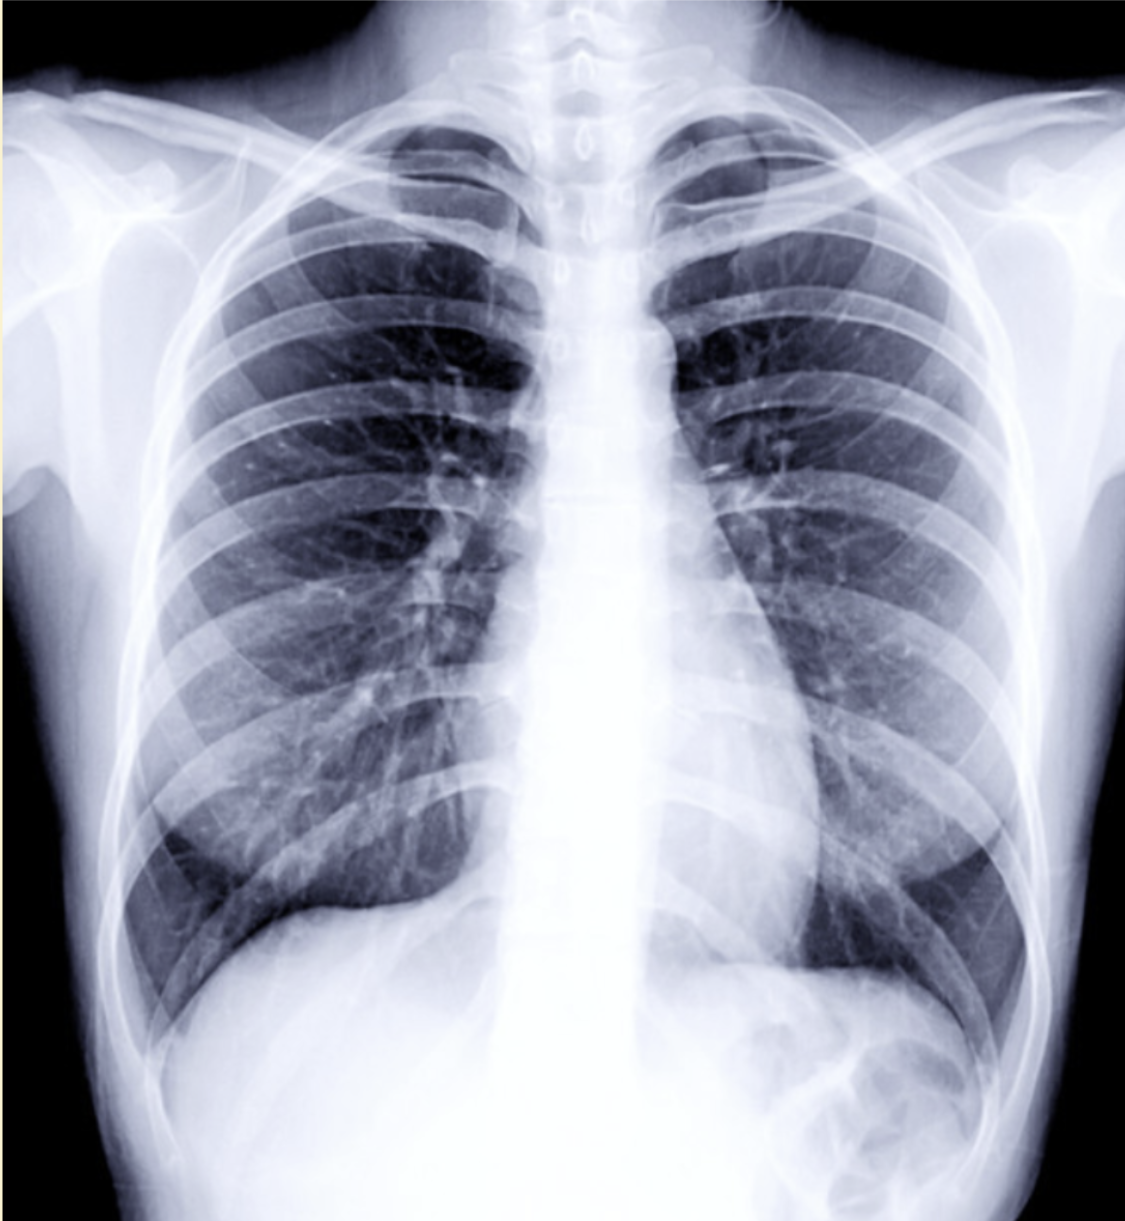

X-ray image of human ribcage

Figure 2. Black-and-white X-ray image showing a human ribcage.

However, X-ray radiography has important limitations. The resulting image is two-dimensional, meaning that all structures along the path of the X-ray beam are compressed into a single flat image. As a result, overlapping tissues can obscure important details, making it difficult to clearly distinguish individual structures. This lack of depth information motivated the development of more advanced imaging techniques, such as computed tomography (CT), which can separate structures in three dimensions. Despite its limitations, X-ray radiography remains a cornerstone of medical imaging due to its speed, accessibility, and diagnostic value, and it laid the foundation for the entire field of bioimaging.